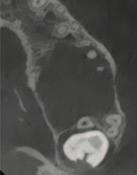

1. What condition is affecting the first permanent molar in Figure 1?

FIGURE 1: What condition is affecting this first permanent molar?